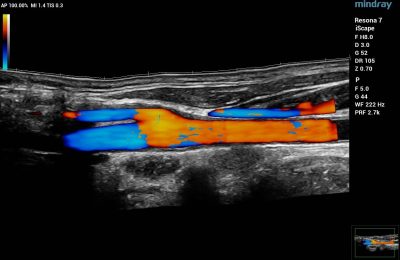

- Blood Vessels – Vascular ultrasound is used to evaluate the circulatory system. CDI is used to diagnose and stage acuity of clots in the veins, as well as venous reflux. It is also useful to assess narrowing and blockages within a patient’s arteries.

Color Doppler of Common Carotid Artery

Color Doppler of Posterior Tibial and Peroneal Veins in the calf